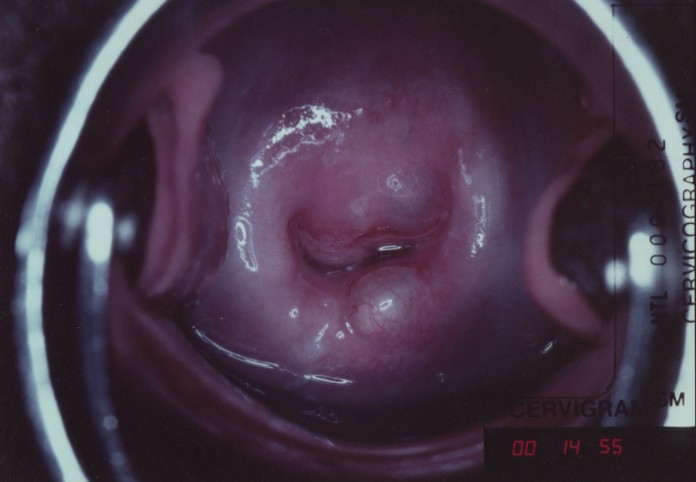

Визуально наботовы кисты выглядят как куполообразные выпячивания желтовато-белого цвета, размером от нескольких миллиметров до двух сантиметров, умеренно-плотной консистенции. Чаще всего локализируются на шейке в зоне трансформации.